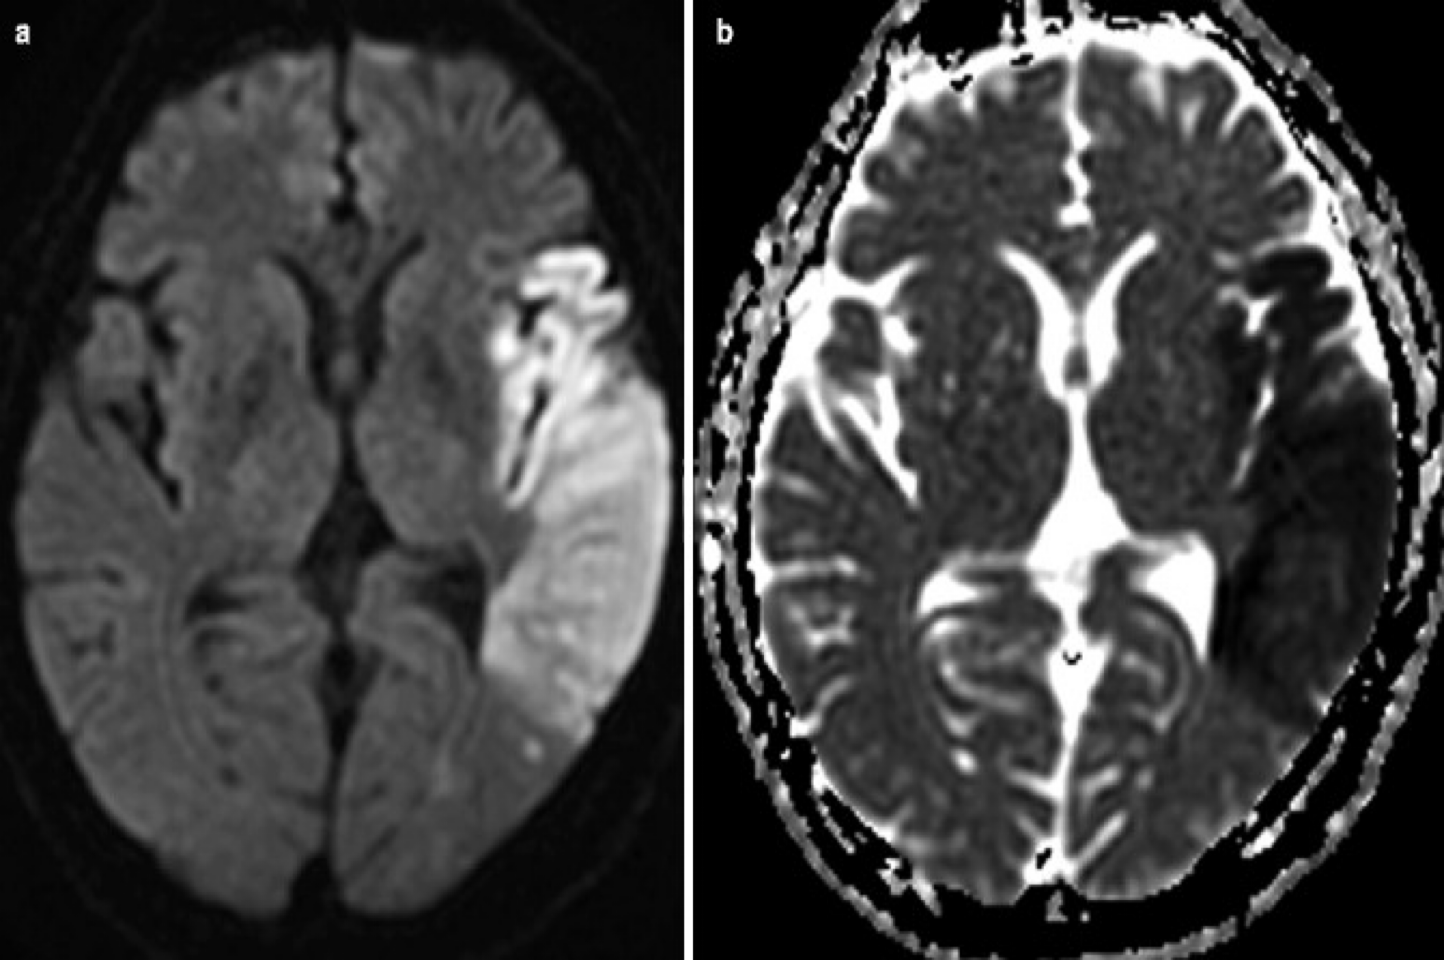

Diffusion weighted images